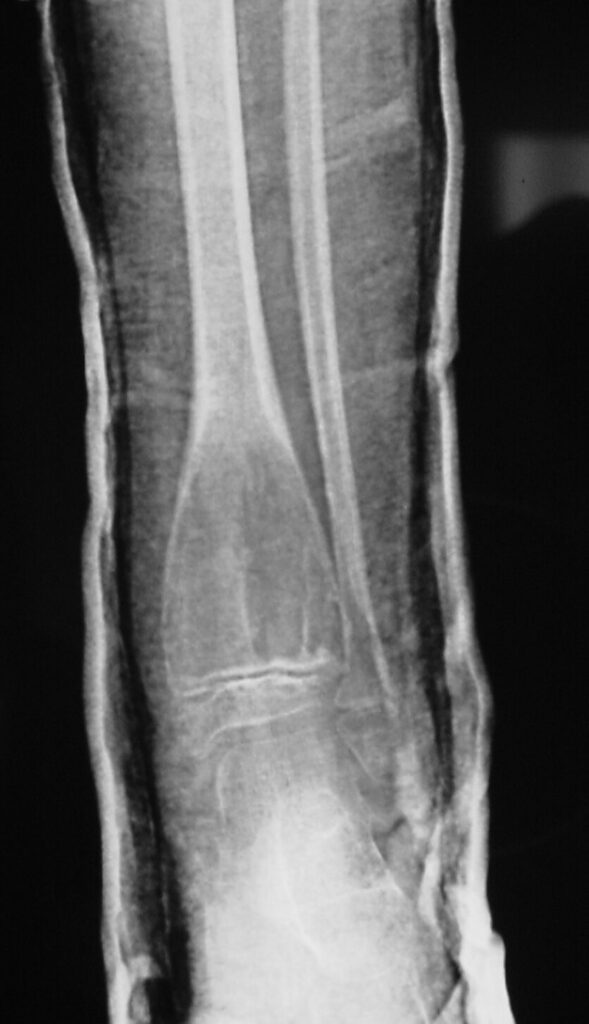

Radiographic Presentation

• Variable sizes

• Multiple internal trabeculations

• Rapid growth

• Cortical scalloping, bone contour often expanded.

Plain x-ray

• Radiolucent

• Geographic and Eccentric lesion that is well circumscribed

• May scallop or expand the surrounding cortex

• Surrounded by sclerotic bone

• Methaphyseal region most common

• Eccentric

• Elevation of the periosteum could be seen as a benign appearing periosteal reaction (continuous periosteal reaction)